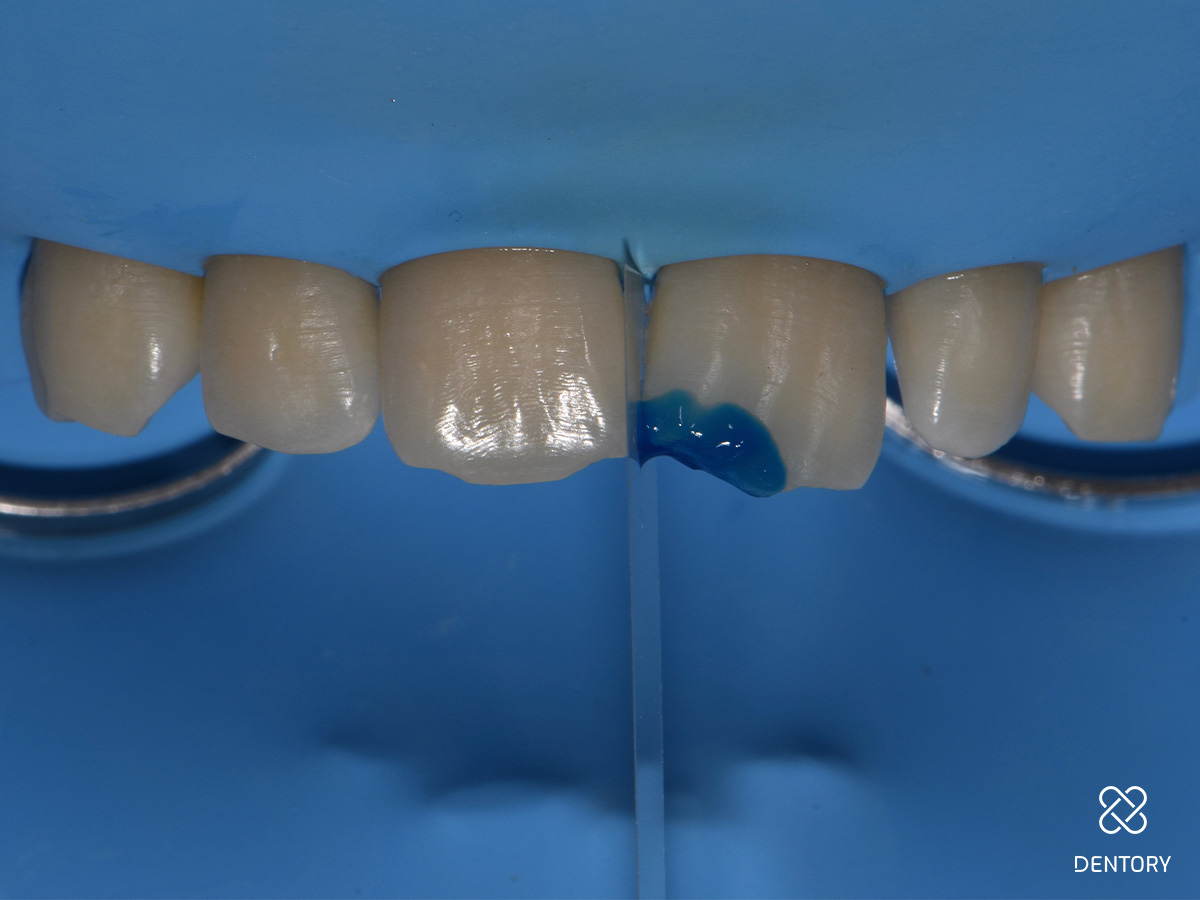

Abbildung 4

Ätzgel (37%) auftragen: Der Verlauf der Anschrägung kann anhand des Ätzgels nachvollzogen werden.